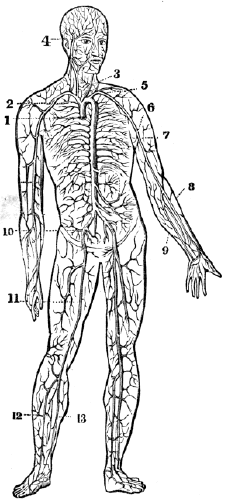

| 17. | Anatomy of the Circulatory Organs, | 154 |

| 18. | Physiology of the Circulatory Organs, | 164 |

| 19. | Hygiene of the Circulatory Organs, | 172 |

| 20. | Anatomy of the Lymphatic Vessels, | 181 |

| 20. | Physiology of the Lymphatic Vessels, | 183 |

| 20. | Hygiene of the Lymphatic Vessels, | 188 |